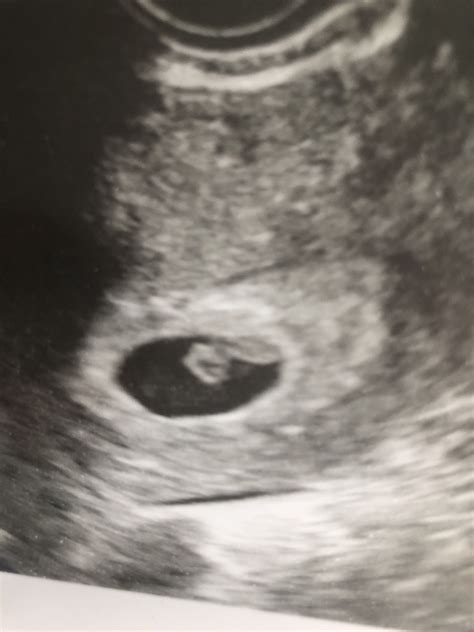

During a 7 week pregnancy sonography, the ultrasound technician will look for several key indicators of fetal development. These include:

• The presence of a gestational sac, which is the earliest sign of pregnancy visible on ultrasound.

• The yolk sac, which provides early nutrition to the embryo.

• The embryo itself, which should be visible as a small, curved structure within the gestational sac.

• The fetal pole, which is the earliest visible part of the embryo.

• The heartbeat, which may be detectable by this week, although it is not always visible at 7 weeks.

If the heartbeat is not detected, it is not necessarily a cause for concern, as it can sometimes be too early to see. The technician will also measure the size of the gestational sac and the crown-rump length (CRL) of the embryo, which helps to estimate the gestational age and ensure that the pregnancy is progressing normally.